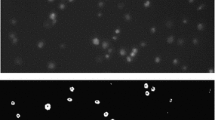

In a focal injury model, platelets adhere and activate under flow on a collagen-coated surface, creating a field of individual platelet aggregates. These aggregates exhibit distinct structural characteristics that are linked to the local flow conditions. By combining image analysis techniques and epifluorescence microscopy, we developed a robust strategy for quantifying the characteristic instantaneous width and length of a growing platelet deposit. We have confirmed the technique using model images consisting of ellipsoid objects and quantified the shear rate-dependent nature of aggregate morphology. Venous wall shear rate conditions (100 s−1) generated small, circular platelet deposits, whereas elevated arterial shear rates (500 and 1000 s−1) generated platelet masses elongated twofold in the direction of flow. At 2000 s−1, an important regime for von Willebrand Factor (vWF)-mediated recruitment, we observed sporadic platelet capture events on collagen that led to rapidly growing deposits. Furthermore, inter-donor differences were investigated with respect to aggregate growth rate. After perfusion at elevated shear rates (1000 s−1) for 5 min, we identified a twofold increase in aggregate size (81.5 ± 24.6 μm; p < 0.1) and a threefold increase in growth rate parallel to the flow (0.40 ± 0.09 μm/s; p < 0.01) for an individual donor. Suspecting a role for vWF, we found that this donor had a twofold increase in soluble vWF relative to the other donors and pooled plasma. Microfluidic devices in combination with automated morphology analysis offer new tools for characterizing clot development under flow.